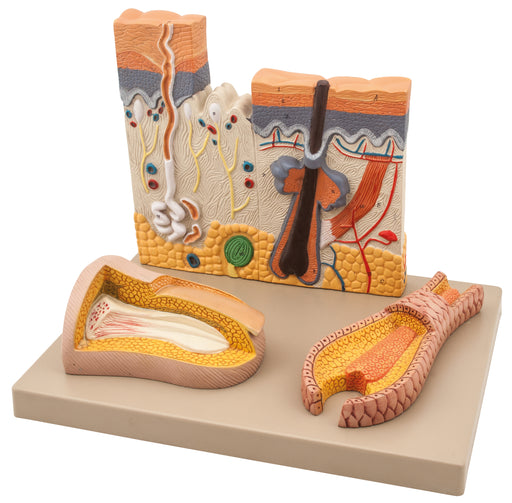

Skin Model - 3 Parts

Skin-hair-nail model with this model it is easy to compare the structures of hairy and hairless skin, sensitive corpuscles, blood vessels, sweat gl...

View full detailsAM16044 -